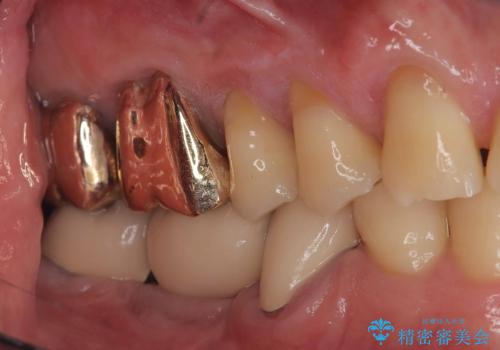

- 治療計画

- 当院にて根管治療を行いましたが、病変の改善が得られなかったため、インプラント治療を行う方針といたしました。

抜歯即時埋入の適応と判断し、抜歯当日にインプラント埋入を行う「抜歯即時埋入」にて処置を実施しました。